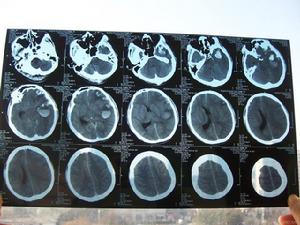

《脊柱脊髓CT讀片指導》基本信息

圖書書名:脊柱脊髓CT讀片指導DVD

內容介紹

ct讀片治療措施